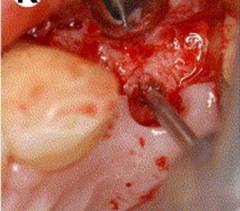

PILOT DRILL

IMPLANT IN SITU

OSTEOINTEGRATE DENTAL IMPLANT SURGERY